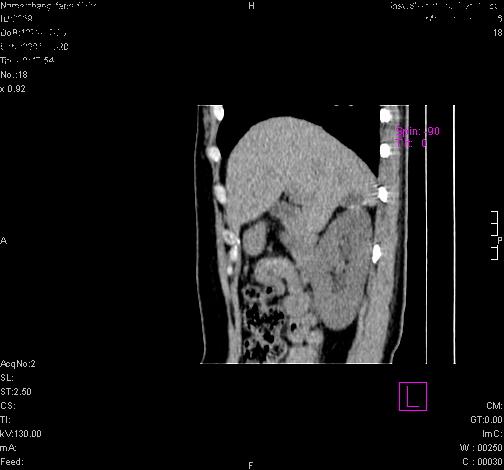

标题: CL0340:【】肾上腺囊肿,比较典型。

患者为年轻女性,查体发现右侧肾上腺囊性占位。无临床体征。

这么漂亮的图像,一看一目了然。典型的右侧肾上腺囊肿,周围有钙化。感谢搂主!

这么明显的弧形钙化,多考虑包虫病所致的寄生虫性囊肿。

右侧肾上腺囊性密度灶囊壁有钙化。考虑肾上腺囊肿,结核?